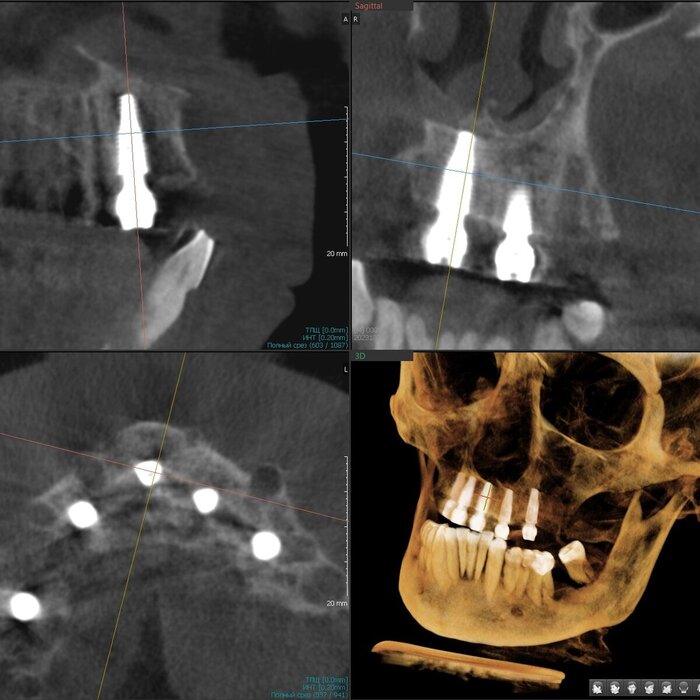

Как же всё-таки у нас происходит это мероприятие? Так как мы вмешиваемся в другую область нашего тела, то стоматолог должен быть хоть немного лором. Разумеется, всё начинается с обследования, которое включает в себя трехмерный снимок, который, в идеале должен захватывать не только зубы и область наращивания, но и носовые ходы с устьями гайморовых пазух и прочими загогулинами, то есть, так называемый остиомеатальный комплекс.

Поэтому кастрированный снимок, где видна только область установки будущего имплантата не прокатит. Тем более в центрах КТ такой снимок стоит дороже классической КТ рублей на 200. И стоит ли экономить?

Анализируя снимок, мы должны принять решение о том можно ли делать синус-лифтинг или отправить его на консультацию к лору. Если всё хорошо, то планируем операцию.

Я делаю транскрестальный синус-лифтинг в 95% случаев последние пару лет, даже если толщина кости меньше 1 миллиметра, но, за счет опыта понимания свойств слизистой гайморовой пазухи наощупь и использования определенных материалов непосредственно в процессе, могу поднять её, зачастую, более чем на 10 мм через дырку диаметром всего 4-5 мм без разреза десны на половину челюсти. Причем, как правило, без использования молотка. Как-то так.

Соответственно разрез меньше, рожа потом практически не распухает, процедура проходит комфортнее, несмотря на её техническую сложность. К тому же мы забываем про риск кровотечения из задней верхней альвеолярной артерии, которая проходит как раз в толще стенки пазухи и часто повреждается при классическом открытом синус-лифтинге. В плане затрат на материал тоже выгоднее, можно сэкономить как собственные деньги, так и деньги пациента. Однако, в голове надо держать то, что данный вид синус-лифтинга требует высоких мануальных навыков врача, ювелирной точности, а также смелости, так как тут шаг влево, шаг вправо-расстрел. Также в любой момент в случае чего нужно быть готовым перевести свой синус-лифтинг в открытый.